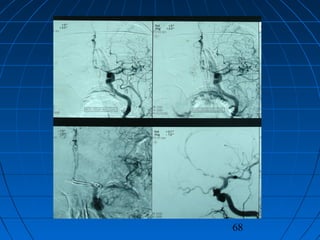

 DÖ: 59 yaşında erkek hastaDÖ: 59 yaşında erkek hasta

 BaşağrısıBaşağrısı (akut şiddetli, son 24 saat(akut şiddetli, son 24 saat

içinde)içinde)

 GKS 14 (WFNS grade 2)GKS 14 (WFNS grade 2)

 Fisher grade IVFisher grade IV

CERRAHİCERRAHİ

 Sol pterional trans-sylvian yaklaşımSol pterional trans-sylvian yaklaşım

 AcomA Anevrizması kliplendiAcomA Anevrizması kliplendi